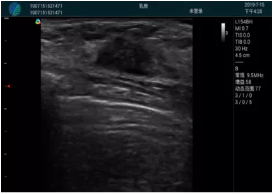

頸動(dòng)脈血流充盈飽滿,無外溢

肝內(nèi)血管顯示清晰,血流敏感無外溢